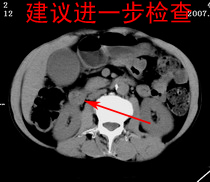

以下是引用zjzjr在2007-9-15 22:24:00的发言:[br]胰头钩突略饱满,肝内外胆管略扩张,胆囊积水.建议增强扫描.

以下是引用代课学生在2007-9-16 10:20:00的发言:[br]胆总管中段以上胆管均示扩张,考虑胆总管下段/胰头部病变,建议增强或micp检查。